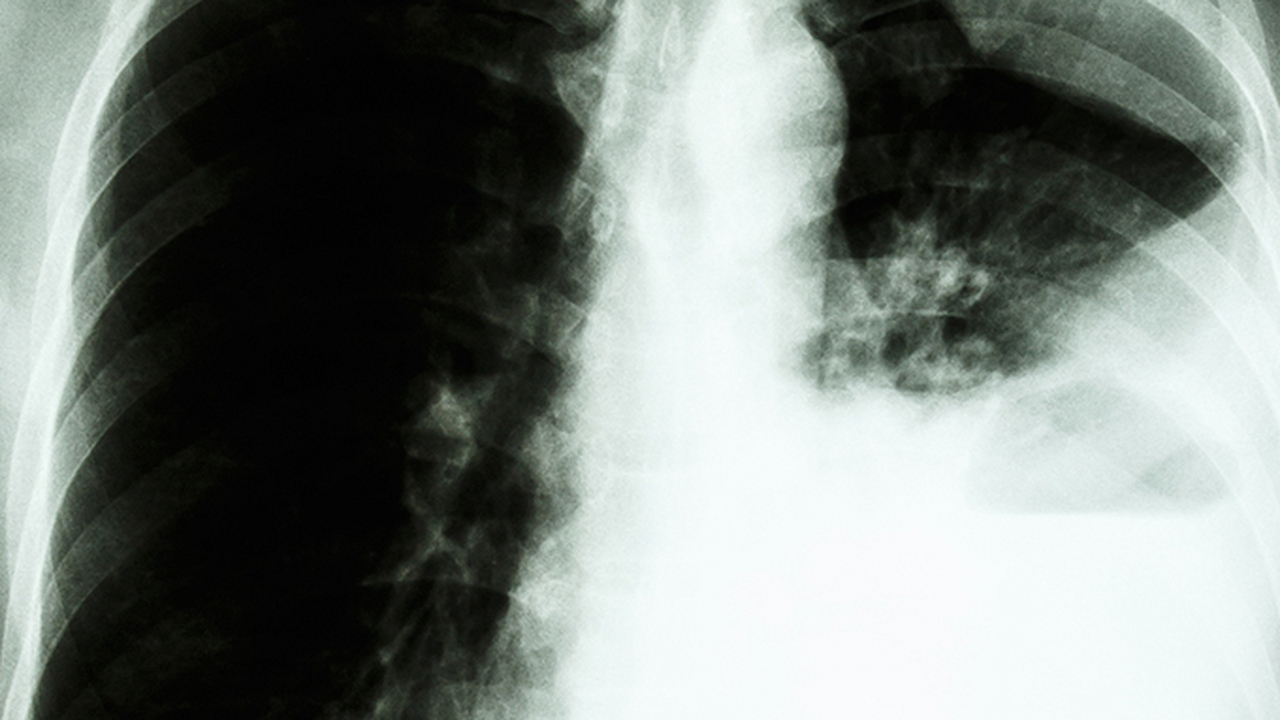

2、重癥肺炎

重癥肺炎可能由細菌、病毒等病原體感染引起,通常表現為高熱、咳嗽、胸痛、呼吸急促等癥狀?;颊呖勺襻t囑使用注射用頭孢曲松鈉、左氧氟沙星氯化鈉注射液、阿奇霉素分散片等藥物治療。重癥肺炎可能導致肺泡通氣不足和氣體交換障礙,進(jìn)而引發(fā)呼吸衰竭。